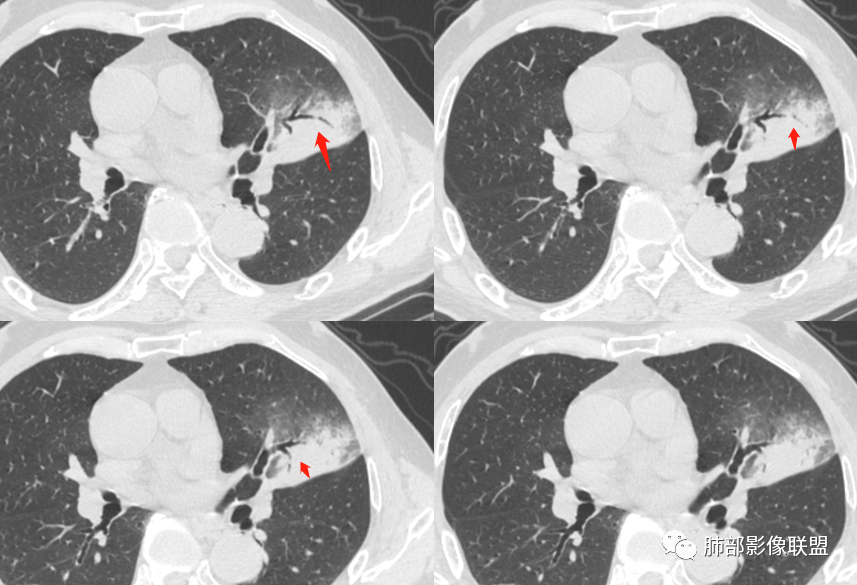

左肺上叶类圆形软组织影,边界较清楚,其内密度均匀,外侧缘可见空气新月征,并可见点状钙化,增强扫描可见均匀强化,病灶周围可见磨玻璃渗出性密度影,斜裂侧光滑平整。考虑炎性病灶,以肉芽肿性炎症为主(如真菌性肉芽肿),鉴别结核(无卫星灶,无多态性),肺癌(无毛刺,分叶等恶性征象,)细菌性炎症(密度一般不这么致密,很少钙化及空气新月征)。

左肺上叶类圆形软组织影,界清,内见空洞影,病灶周围斑片影,可见空气支气管征,未垮叶。考虑炎性病变,糖尿病四大金刚,肺克?毛霉?

老年男性,血糖升高六年,反复咳痰咳嗽3周,左肺上叶近斜裂类圆形肿块影,边缘伴磨玻璃影,边界不清。内部可见支气管走行、钙化、小空洞,叶间裂局部膨隆,增强扫描轻度强化,内部可见小的低密度区,边界尚清。考虑为炎性病变可能性大。

左肺叶裂旁实变影,宽基底与叶裂胸膜相连,边缘平直,部分略膨隆,病灶近段及上段支气管深入病灶内,部分壁略增厚,远端支气管截断,似有小空泡,壁规则,内部可见高密度钙化,周围可见模糊的GGO,血象正常,考虑结核(NTM),鉴别隐球菌,奴卡,放线菌。

老年男性,66,反复咳嗽、咳痰3月。糖尿病,血象不高。

胸部CT:左肺上叶类圆形肿块影,边界较清楚,密度较均匀,内可见小片坏死、偏心空洞、空气新月征、点状钙化,周围晕、絮状渗出、边缘模糊,支气管扩张、充气征、支气管进入病灶堵塞,叶裂牵拉明显,增强扫描中度均匀强化,纵隔可见淋巴结。考虑:炎性病灶,肉芽肿性炎症,曲霉?毛霉?鉴别:TB,淋巴瘤。

左上肺类圆形肿块影,边界较清楚,支气管通畅略扩张,周围磨玻璃影,其内密度均匀,外侧见空气新月征,且见点状钙化。叶间裂光滑稍膨隆。老年男性,糖尿病,高血压,痰培养克雷伯菌。综合考虑炎性病灶,克雷伯合并真菌感染,曲霉。结核合并真菌。鉴别肺癌合并感染。

左肺上叶类圆形软组织影,边界稍模糊,其内密度均匀,外侧缘可见空气新月征,并可见点状钙化,增强扫描渐进性强化,病灶周围可见磨玻璃影,斜裂侧光滑平整,气管未见明显闭塞,淋巴结未见肿大,糖尿病患者,首先考虑感染性变,结核并曲霉?